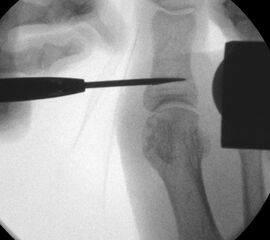

• Notwendigkeit der intraoperativen Bildvestärkerdiagnostik.

• Bildverstärker.

Operationstechnik (Text und Fotos)